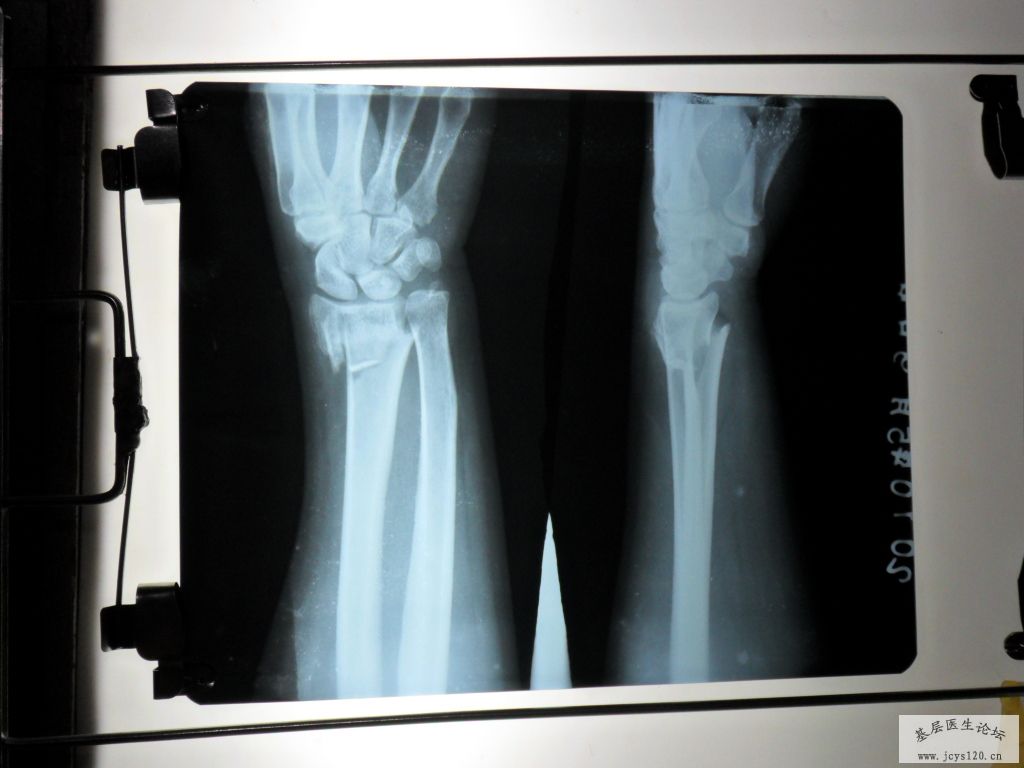

桡骨远端粉碎性骨折复位前后对比!一小时前急诊的病例!

一小时前,有一妇女因为去田间放水,不慎摔倒在田埂上,摔倒时因害怕伤着头,条件反射式的将右手撑在地上,右手剧烈疼痛,所以来诊,给予急诊X光摄片,呈右手远端粉碎性骨折,断端重叠移位,并有小块碎骨片嵌插在断端,片照好后,由我和助手握住右手骨折端两侧开始徐徐用力做拔伸牵引,我估计到重叠的断端分离后,将患者的手呈后前位,(掌心向上),再在骨折端施行了正骨八法中的某些手法,复位好后,敷上中药,夹板,再复查了一张X光片子,15分钟后,片子出来一看,复位一次成功,达到功能复位,随后开了3天的西药让病人回家去了,以下是该患者的片子:

很常见的骨折,每月都能碰到,复位不错但骨折远端仍向背侧有少许移位,固定时用科雷氏夹板固定掌屈位位置会更好。用石膏固定尺偏掌屈位也行。